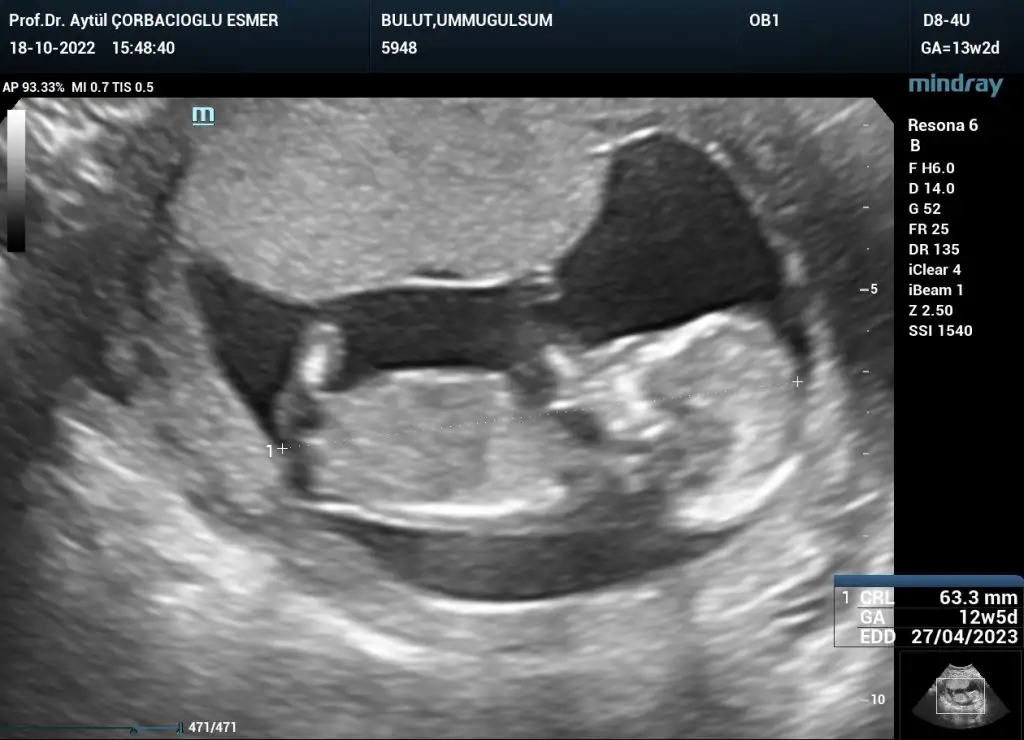

Kızlar selam kontrolden çıktım her şey yolunda çok şükür 15+4 kısa kısa ben de bahsedilenlere ben de cevap vereyim;

Son olarak yakışıklı oğlumu bırakıyorum buraya teyzeleri, hepinizi öpücükler🤍